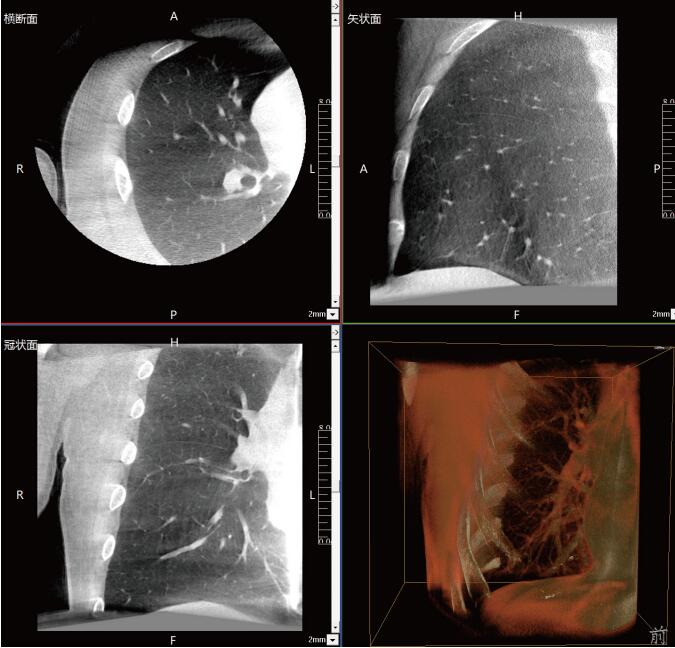

近年來,在肺部手術領域的應用呈現(xiàn)出顯著的增長態(tài)勢。這一技術不僅滿足了臨床指導穿刺、精準確認病變與針尖位置關系的迫切需求,更通過大量臨床研究的驗證,證明了其在肺結節(jié)診斷、定位及治療中的有效性和安全性。

《中國專家對CBCT引導下肺結節(jié)的診斷、定位和治療的共識》提到C型臂CT系統(tǒng)憑借其強大的功能,能夠充分滿足透視監(jiān)測、病變與工具位置確認、消融區(qū)監(jiān)測以及并發(fā)癥檢查等多元化的臨床需求。因此,在考慮設施條件(如導航設備、手術室空間)、靶病灶特性(大小、密度)、麻醉方法及干預路徑(經支氣管或經胸)等多重因素的基礎上,C型臂CT系統(tǒng)成為了眾多醫(yī)療機構的優(yōu)選方案。

呼吸介入C型臂CT的臨床適應癥廣泛,包括支氣管鏡檢查、肺結節(jié)穿刺活檢、肺結節(jié)定位、肺結節(jié)消融以及經支氣管肺結節(jié)診療等多個領域。其臨床應用價值不言而喻:在經支氣管干預肺結節(jié)時,透視功能可精準引導支氣管鏡與活檢鉗直達靶結節(jié);重建的三維圖像則能清晰展示干預工具的位置,確保操作的準確性。在肺結節(jié)消融過程中,呼吸介入C型臂CT更是實現(xiàn)了高精度定位,有效提升了治療效果。